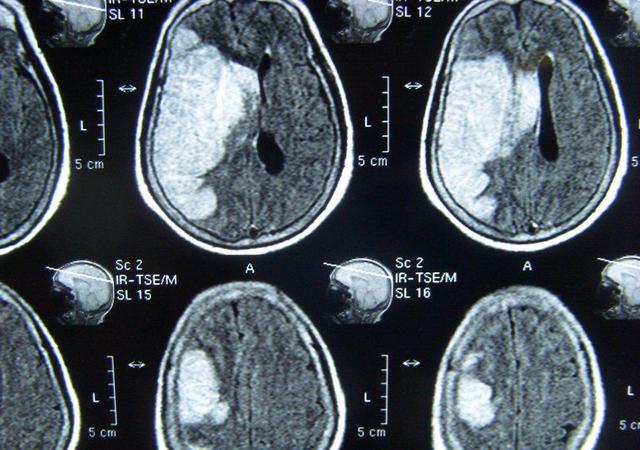

「脳卒中」は中国医学の概念で、中臓と中経に分けられ、中臓は現代医学でいう脳出血に相当し、中経は急性脳梗塞に相当する。脳出血も脳梗塞も非常に重篤な脳血管疾患であり、脳出血の死亡率と後遺障害率は非常に高いが、脳梗塞の死亡率は脳出血より低いが、後遺障害率も非常に高く、脳出血と脳梗塞の患者の大部分は四肢片麻痺、言語障害、嚥下障害などの後遺症を残す。

これらの後遺症が回復するかどうかは、まず出血量や脳梗塞の大きさや部位と密接な関係がある。例えば、一度に数十ミリリットルというような大量の脳出血が、手足の運動をつかさどる脳組織の部位に起こった場合、出血の圧迫により、この部位の脳神経は非常に早く損傷を受け、神経の損傷は不可逆的であるため、症状はすぐに現れ、回復することは容易ではありません。もう一つの例は大規模な脳梗塞で、これも同じ理由で、脳神経の損傷による急性の虚血で、この時、もし適時に血栓溶解で血管を再び痛めさせれば、脳組織の損傷はさらに悪化せず、比較的軽い程度にとどまり、手足の症状も軽く、その後、運動の回復を通じて、正常に近いレベルまで回復することができる。

脳出血の後、血栓が周囲の脳組織を圧迫し、水腫で死んでしまうことがある。血液の量が比較的多い場合は、うっ血を取り除くために頭蓋骨を開けなければならず、脳組織がさらに損傷しやすくなる。

脳梗塞の後、脳組織は血液と酸素の不足で死んでしまい、柔らかくなった後、おそらく小さな空洞かそこに液体が溜まっただけだろう。

実際には、脳組織の損傷の程度、大きさ、場所に関係している。

損傷の程度が比較的軽い場合、ある部分が損傷していても、その部分には深刻な損傷を受けていない脳組織が点在しているため、これらの脳組織はまだある程度の機能を持ち、身体を弱く制御することができる。時間の経過とともに、これらの軽度の損傷を受けた脳組織が徐々に回復し、元の脳組織全体の機能を引き継ぐようになると、中枢制御が再び確立され、身体は自然に回復する。

損傷した脳組織が比較的小さければ、たとえ一つの機能が完全に損なわれていたとしても、周囲の脳組織は時間の経過とともに細胞を分化させ、死滅した脳組織の機能を引き継ぐようになる。